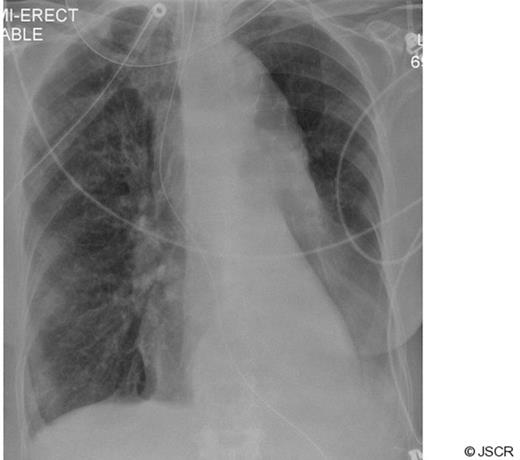

Arterial oxygenation improved quickly afterwards, allowing the inspired fraction of oxygen to be reduced to 0.3, and there were no complications from the procedure. A subsequent radiograph confirmed re-inflation of the left lung field (Fig 4).